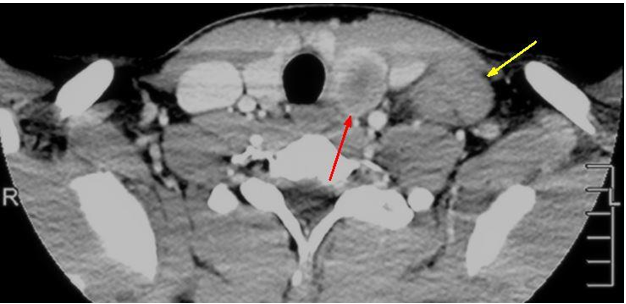

Papillary thyroid cancer has the fastest increasing incidence of any thyroid malignancy and accounts for the majority of thyroid neoplasms (75-85%). It is also the most common type of thyroid cancer to develop from radiation exposure1. Papillary thyroid cancer typically occurs in caucasions and has a female predilection (3:1 ratio), with a peak age of incidence between 25-50 years-old. It commonly presents as a painless neck mass. While no specific laboratory tests exist for diagnosis, elevation in thyroxine, triiodothyronine, or TSH can be seen. Radiology plays a crucial role in the diagnosis of papillary thyroid cancer, with ultrasound being one of the initial steps in the workup. Radioiodine (I-131) nuclear medicine studies can be used to check for distant metastases and ablate thyroid cancer. Thyroid lobectomy is the main treatment, with total thyroidectomy being reserved for higher risk tumors. We report an unusual clinical presentation of the diffuse sclerosing variant of papillary thyroid cancer in a 16-year-old male, who presented with a painless neck mass that had been growing over the past year. The patient subsequently received a total thyroidectomy and radioiodine treatment.References